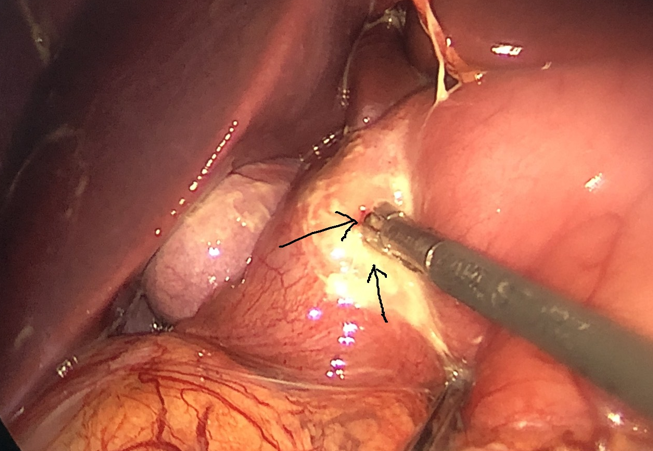

Trong quá trình phẫu thuật nội soi

quan sát thấy ổ bụng chứa nhiều dịch mủ bẩn lẫn dịch tiêu hóa, kiểm tra phát hiện

1 lỗ thủng mặt trước dạ dày đường kính 2 cm, quanh lỗ thủng xơ trai, bằng kinh

nghiệm và tay nghề của các bác sĩ phẫu thuật, bệnh nhân đã được khâu kín lỗ thủng,

lấy dịch bẩn, làm sạch ổ bụng.

Lỗ thủng dạ dày